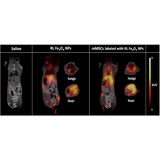

Combining PET with MRI enhances the capabilities to study detailed morphological changes in different organs and tumours, adding more precise information of the distribution and behaviour of the PET tracer.

Bruker’s sequential PET/MR instruments are offered at 3T for translational research and at 7T and 9.4T for high-field applications in mice and rats using Bruker’s BioSpec Maxwell MRI technology. This is combined with Bruker’s SiPM PET technology, providing the highest sensitivity, high spatial resolution and precise quantification across the entire FOV. A touch screen controlled motorized animal transport system simplifies the workflow and supports a broad spectrum of application fields, such as oncology, functional and anatomical neuroimaging, cardiac imaging and stroke models. All of this powered by the Paravision 360 software, allowing MRI users to follow familiar MR imaging workflows to obtain valuable PET/MR data immediately.